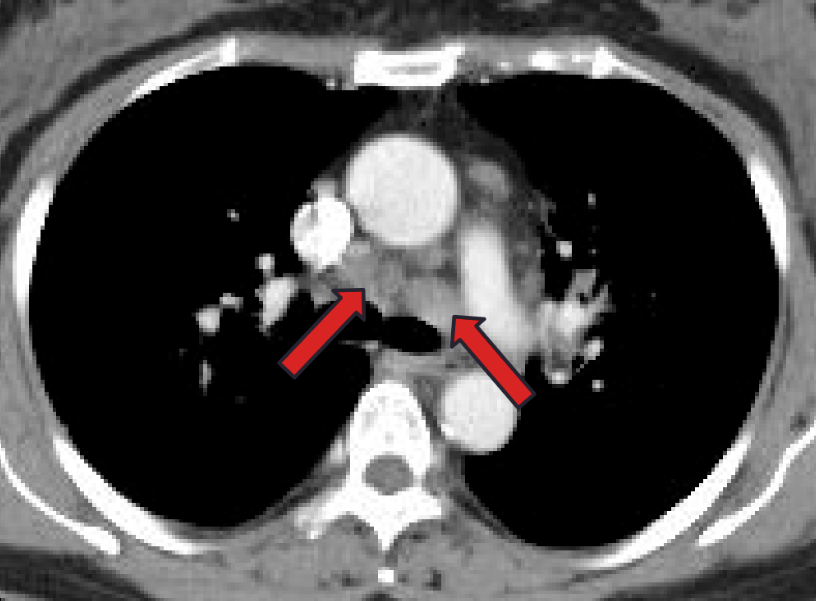

2024-08-26 停用甲泼尼龙。09-04胸部增强CT:两肺门及纵隔多发小及增大淋巴结,较06-12片部分稍大。继续停药。

2024-12-09 胸部CT:纵隔及肺门多发淋巴结肿大,两肺多发病变,均较09-04片进展;ACE阴性。考虑结节病复发,再次启动糖皮质激素治疗,方案:甲泼尼龙32mg qd×1周、28mg qd×2周、24mg qd维持。

2025-01-22 胸部CT:较24-12-09片肺内病灶吸收,纵隔淋巴结缩小。激素减量方案:甲泼尼龙20mg qd×3周、16mg qd维持。